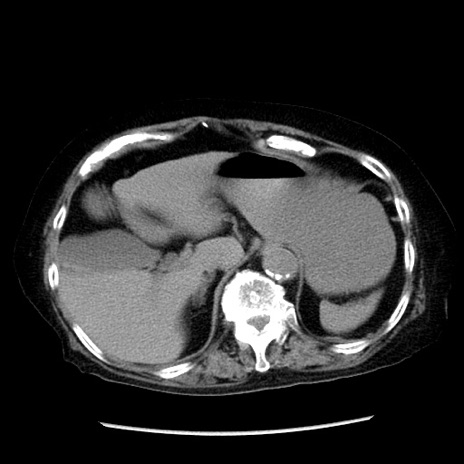

冠状断像

【症例】 90歳代女性

【主訴】 腹痛・嘔吐

【現病歴】今朝から左側腹部痛を認めた。 経過観察していたが、嘔吐を認めたため来院。

【既往歴】 子宮癌術後

【身体所見】 意識清明、BP 127/54mmHg、P 98bpm Sp02 95%(RA)、BT 35.8°C、腹部平坦・軟腸ぜん動音聴取良好、右下腹部圧痛(+) 反跳痛なし

【データ】WBC 9800、CRP 0.46